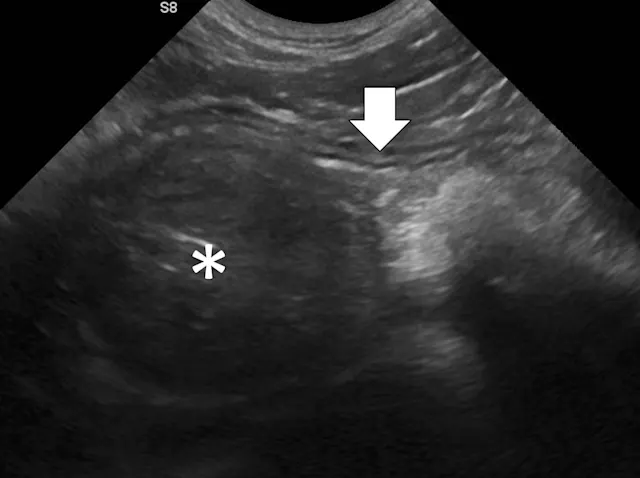

Small Intestinal Mechanical Obstructions

Small intestinal mechanical obstructions occur when a foreign body blocks the lumen of any segment of the small bowel, causing segmental dilation located orad to the foreign body (Figure 3).9-12 As the small bowel increases in size, it crowds the peritoneal cavity and begins stacking on itself with sharp, hairpin turns.9-12 Dilated portions of the small bowel usually contain a mixture of fluid and gas. One study demonstrated that a serosal-to-serosal jejunal diameter of >1.5 cm helped discern dogs with and without mechanical obstruction.1 Dilated bowel can often be followed to the site of obstruction, where it immediately normalizes aborad to the foreign body. In some patients, the foreign body may not be visualized if located deep to more superficially located gas-dilated intestines. In patients scanned in dorsal recumbency, gravity may cause heavier foreign bodies to settle deep in the abdomen. If jejunal dilation >1.5 cm is present but the site of obstruction is not initially seen, the patient may be shifted into right and then left lateral recumbency and the midabdomen reinterrogated. In addition, one study suggested that a foreign body may be palpated in a majority of cases13; physical examination may therefore expedite ultrasonography. If the foreign body can be manually held or trapped against the body wall, ultrasonography can be performed on that location; however, identifying the site of obstruction is not always necessary if segmental dilation is present and the clinical picture supports a diagnosis of mechanical obstruction.

Abdominal ultrasound of a 9-month-old spayed Australian cattle dog with a surgically confirmed small intestinal mechanical obstruction. There is moderate small intestinal dilation (asterisk) with hyperechoic fluid, ingesta, and gas measuring 2.1 cm in diameter at the level of the white calipers oral to a pecan foreign body (pound sign) that is visible as a hyperechoic surface with distal acoustic shadowing. The small intestine is normal and not dilated immediately aboral to the foreign body (arrow), with a small volume of intraluminal gas causing reverberation artifact.